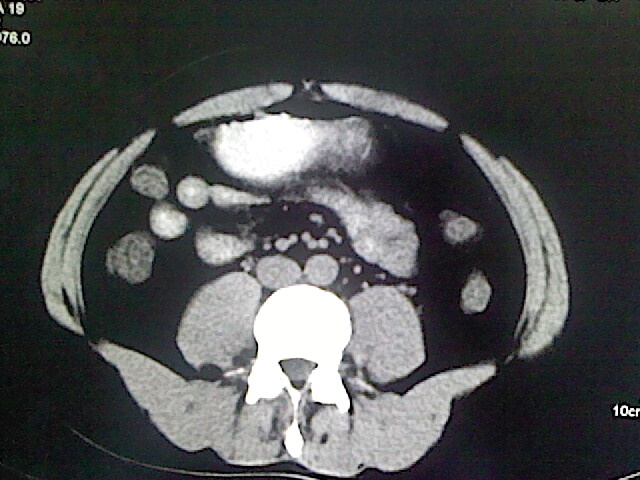

以下是引用卜一在2009-3-14 9:49:00的发言:[br]胆囊萎缩,胆囊壁不规则增厚,内部结构模糊,增强明显强化。另:肝左叶外侧段肝囊肿。支持:慢性胆囊炎!高度可疑:胆囊癌!

以下是引用余辉在2009-3-14 8:48:00的发言:[br]1)慢性胆囊炎。2)肝左叶外侧段肝囊肿。3)脂肪肝。[br]支持,胆囊萎缩,密度增高,不知b超具体有何提示,钙胆汁?结石?

以下是引用jiangjing在2009-3-14 10:18:00的发言:[br]1)慢性胆囊炎。2)肝左叶外侧段肝囊肿。3)脂肪肝。4.】建议行肝功能检查